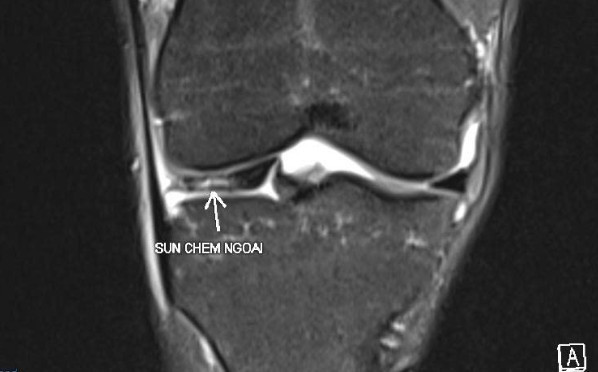

Ngoài ra, việc chơi pickleball liên tục trong thời gian dài cũng khiến nhiều người phải nhận “trái đắng”. Báo Nhân Dân đã đưa tin về trường hợp nữ bệnh nhân 32 tuổi mới chơi pickleball được 3 giờ liên tiếp thì đau khớp gối dữ dội, chụp MRI cho thấy rách sụn chêm dạng phức tạp, mảnh sụn di lệch vào trong khớp gây “kẹt gối”. Phẫu thuật nội soi được triển khai ngay để cứu phần sụn còn lại.

Cố gắng cứu bóng khi chơi pickleball, nhiều người phải cấp cứu- Ảnh 3.

Hình ảnh MRI tổn thương rách sụn chêm. (Ảnh: Báo Nhân dân)